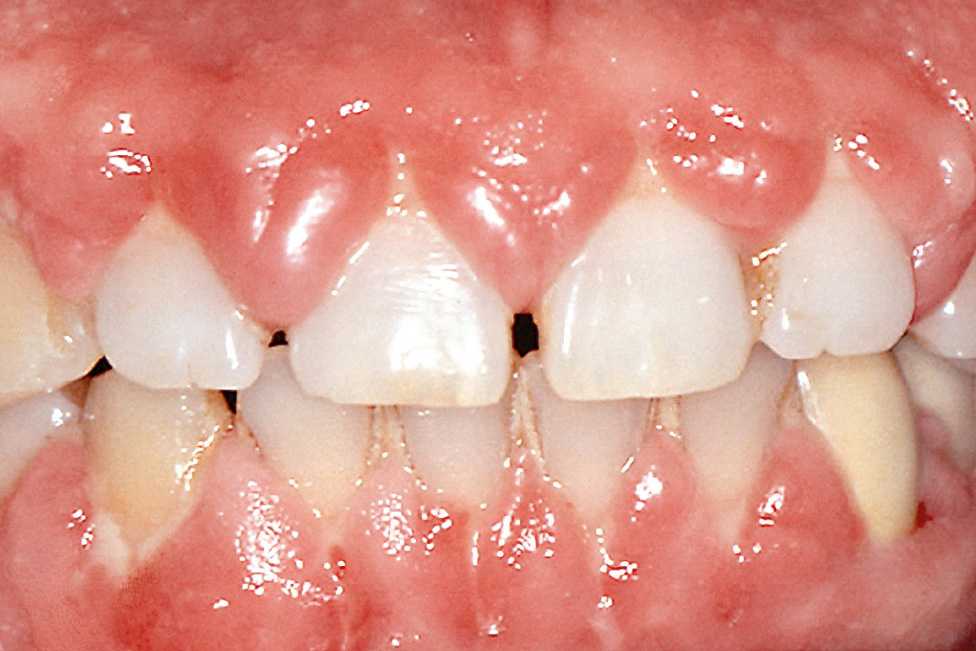

Die Gingivavergrößerung ähnelt klinisch und histologisch der hydantoininduzierten Wucherung und manifestiert sich am ausgeprägtesten im Bereich der labialen Papillen (Abb. 5). Die Veränderungen bilden sich nach Absetzen des Medikaments häufig wieder zurück. Durch eine regelmäßige Entfernung der Plaque ist es möglich, das Ausmaß der Wucherung deutlich zu reduzieren und oft auch vollständig zu eliminieren.

Abb. 5 Gingivawucherung bei Medikation mit einem Kalziumkanalblocker.